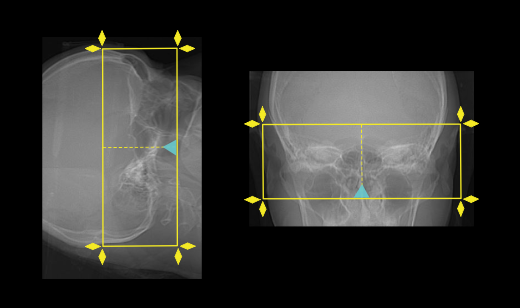

- Plan the scout starting point (laser indicator) at the upper lip of the patient.

- Plan the scan range to include the temporal bone that covers superiorly from the bony part of the IAM-covering the most superior mastoid air cell to mastoid tip inferiorly.